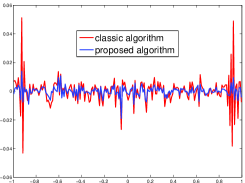

Noised projection data: In order to show the ability of noise suppressing, we apply the algorithms to noised projection data. For the noise experiments, the iteration procedures were terminated the algorithms when for 60, 90 and 120 projections. The reconstruction images were given in Fig. 5, and Table 2 showed the MSE, number of iterations, running time of different images in Fig. 5.

| Algorithm | TV-S | TV-PPS | TV-S | TV-PPS | TV-S | TV-PPS |

|---|---|---|---|---|---|---|

| projections | 120 | 120 | 90 | 90 | 60 | 60 |

| iterations | 49 | 49 | 34 | 33 | 25 | 24 |

| MSEs | 0.0134 | 0.0108 | 0.0132 | 0.0085 | 0.0192 | 0.0112 |

| RT(min) | 5.6175 | 6.6477 | 2.8230 | 2.5867 | 1.5444 | 1.4879 |

By comparing Fig. 5 and Table 2, we can observe the reconstructed images by the proposed superiorization algorithm have higher quality than these by classic superiorization algorithm. Therefore, the performance of the proposed superiorization algorithm is better than the classic superiorized algorithms for noised projection data.